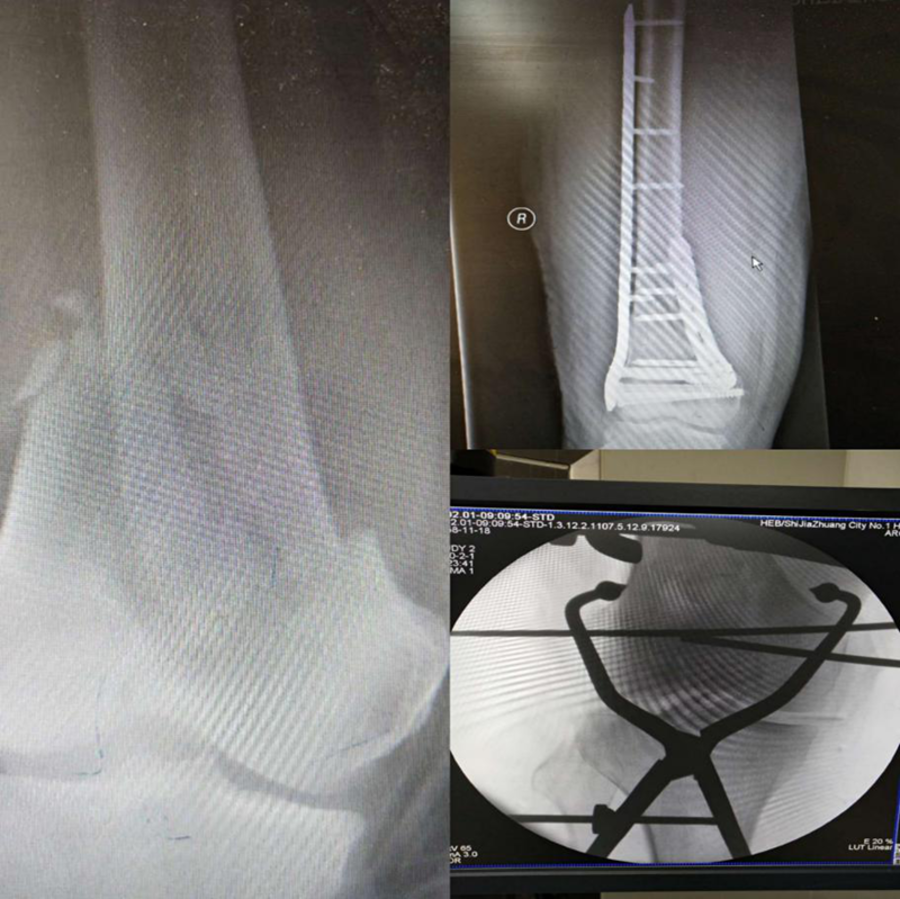

骨科刘晓辉主任完成的骨折复位内固定手术